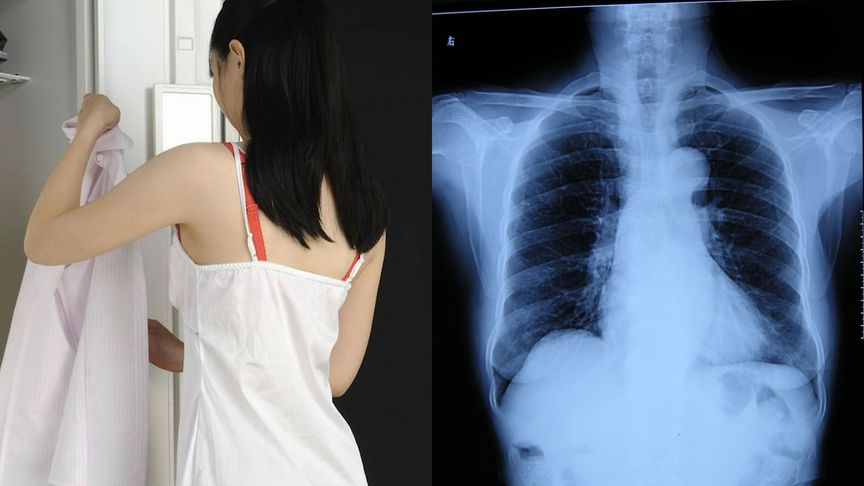

女孩拍x光被要求脱光上衣医生停职来检查没男女之分

图片尺寸864x486